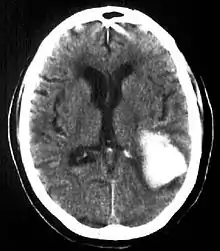

| Multiple intraparenchymal hemorrhage | |

Intraparenchymal hemorrhage accounts for approximately 8-13% of all strokes and results from a wide spectrum of disorders. It is more likely to result in death or major disability than ischemic stroke or subarachnoid hemorrhage, and therefore constitutes an immediate medical emergency. Intracerebral hemorrhages and accompanying edema may disrupt or compress adjacent brain tissue, leading to neurological dysfunction. Substantial displacement of brain parenchyma may cause elevation of intracranial pressure (ICP) and potentially fatal herniation syndromes.